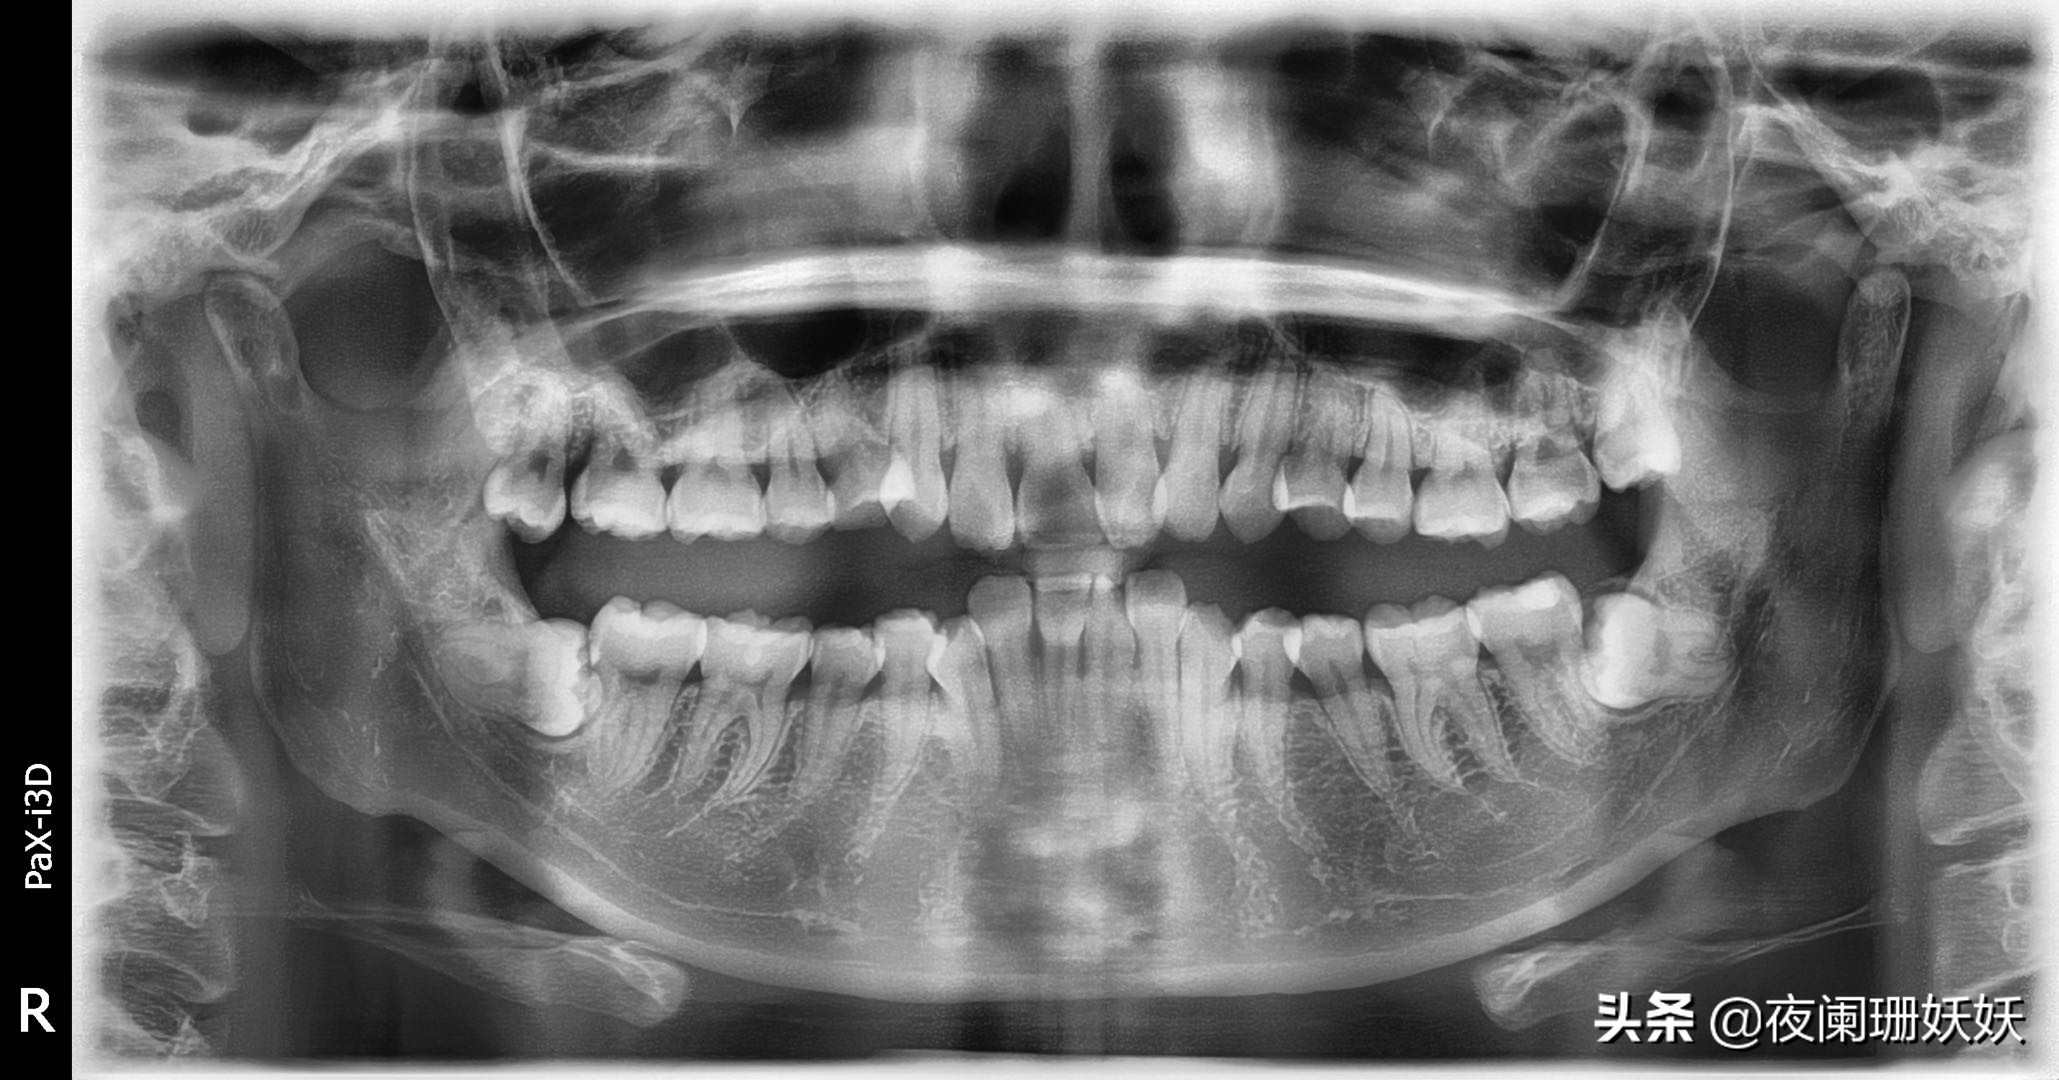

医生说我左边牙更难拔,跟隔壁牙根重影了,怕会挤到隔壁牙神经,隔壁牙也就保不住了。妈呀!好怕怕啊。。

上了药,缝了两针,感觉把脸给缝一起了,由于麻药的作用,并没有感觉疼。。塞了块药棉,让我咬半个小时吐了,让我去诊所打点滴,输点消炎药,拔牙两千块钱,这还是看在我同学的面子上优惠了,中间拍片子拍了三次,都没给记钱,交了钱回家了。两点半去的,三点开始拔牙的,离开时五点了。。整整拔了两个小时!!!